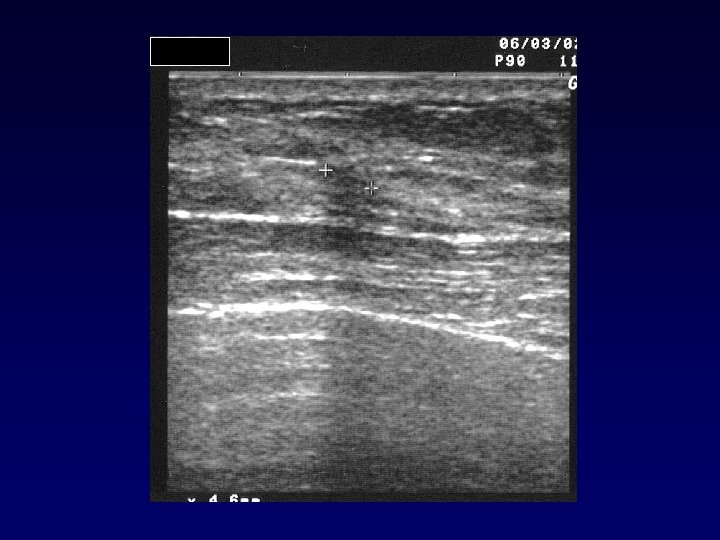

Valeur de l’échographie de deuxième intention

Valeur de l’échographie à postériori • Elle retrouve une lésion passée inapercue dans 23% à 57% des cas • Un rehaussement a d’autant plus de chance d’être un cancer : – qu’il existe un substratum échographique (43% versus 14%) • L’écographie de second look rattrape plus les cancers invasifs que in situ (58% versus 29%) : La. Trenta Radiology 2003